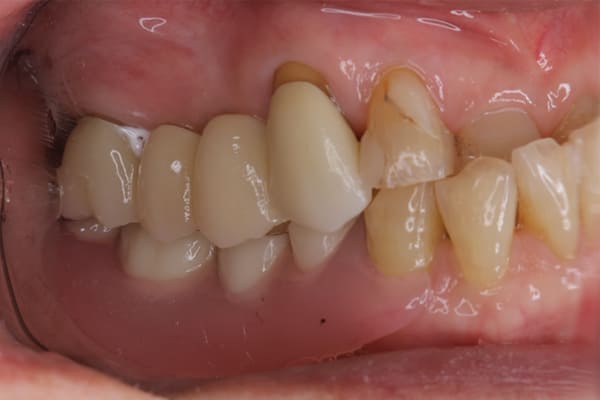

症例レポート[CASE.01]

義歯が合わず痛い、

見た目も気になる

- 性別・年齢

- 女性(40代)

- 主訴

- 下の義歯が合わず入れると痛みがある、見た目も気になるので外にはつけていかない

- 治療

- 下顎精密金属床部分入れ歯

- 治療期間

- 約2か月間

- 費用

- 55万円(税込)

入れ歯が沈み込むことを防止するストッパーがない入れ歯を装着されていたため、お食事により入れ歯が沈み込みお痛みがでている状態でした。

笑った際に、太いバネが左右に見えるため、あまり大きく笑うことを避けていらっしゃいました。

作製した入れ歯は、お食事の際に入れ歯の沈み込みを予防するため、適切なストッパーを付与することで、入れ歯は沈み込まなくなり、お痛みは消失しました。

右下のバネの位置は後ろに、左下のバネは見えづらい形態のバネを用いる設計とすることで笑った際にバネが見えないようになり、気にされることはなくなられました。

裏側の見えない部分は金属を用いることで、お食事の際の入れ歯の動き、沈み込みを抑えお痛みがでづらく、入れ歯の動きが抑制されることで、長期的に残りの歯に負担のかかりにくい設計としました。